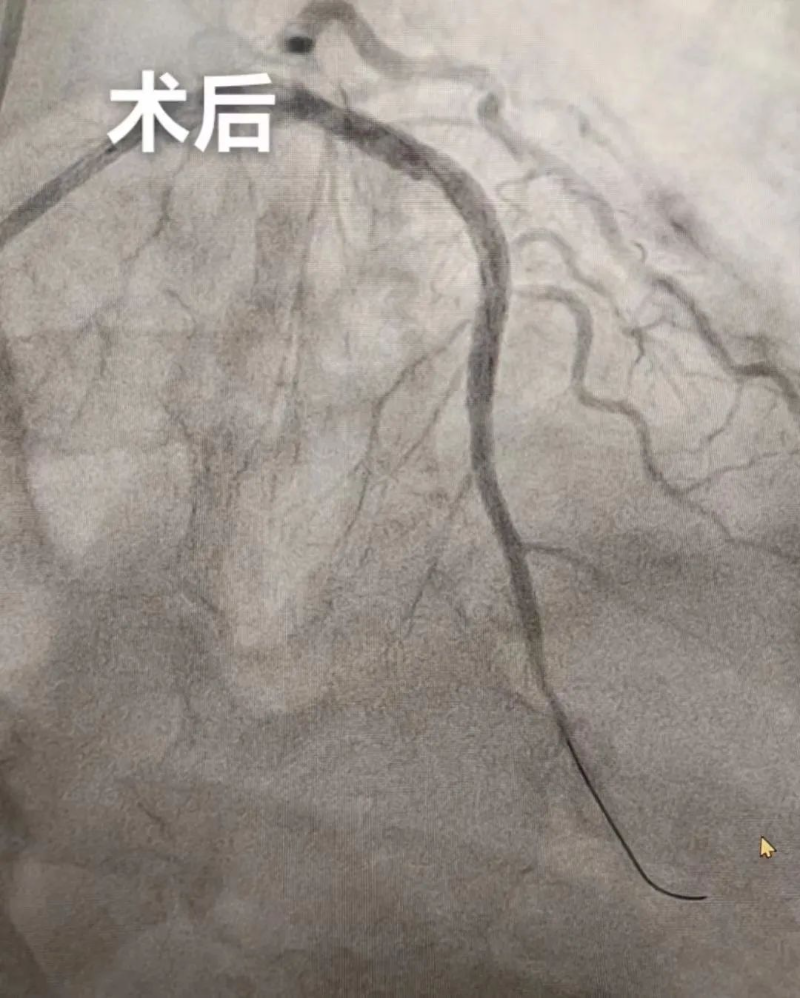

9月19日晚上,新院心血管内科为一名急性广泛前壁心肌梗死患者行支架植入术,成功挽救了患者的生命,阻止了病情的继续恶化,这也是我院整体搬迁至新院后的首台介入手术,标志着新院介入室正式启用,迈入一个新起点。

家住杨村80岁的李大爷(化名)胸口疼痛呈压榨性,疼痛症状持续不能缓解。家属送李大爷到杨侨镇卫生院就诊,心电图结果提示广泛前壁ST段抬高,杨侨镇卫生院通过分级转诊微信工作群传送心电图,经我院心血管内科杨世映副主任医师远程会诊,确诊为急性广泛前壁心肌梗死,建议绿色通道双绕行急诊PCI。

随后,杨侨镇卫生院立即护送李大爷转诊至我院,送入介入室,介入团队快速完成急性心梗支架植入术,门球时间20分钟。术后,李大爷转危为安。